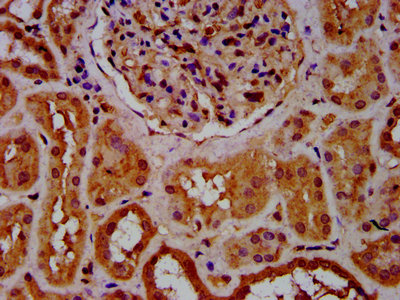

IHC image of CSB-PA773062LA01HU diluted at 1:600 and staining in paraffin-embedded human kidney tissue performed on a Leica BondTM system. After dewaxing and hydration, antigen retrieval was mediated by high pressure in a citrate buffer (pH 6.0). Section was blocked with 10% normal goat serum 30min at RT. Then primary antibody (1% BSA) was incubated at 4°C overnight. The primary is detected by a biotinylated secondary antibody and visualized using an HRP conjugated SP system.